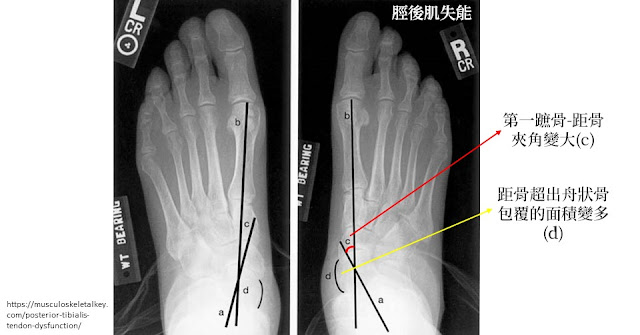

● 放射影像:距骨-第一蹠骨夾角增加、距骨半脫位、跟骨-骰骨外展角度變大。

● 放射影像:距骨-第一蹠骨夾角增加、距骨半脫位、也可能看到退化出現。

X光可以看到右腳的第一蹠骨和距骨的夾角變大,距骨超出舟狀骨包覆的面積也變多 |